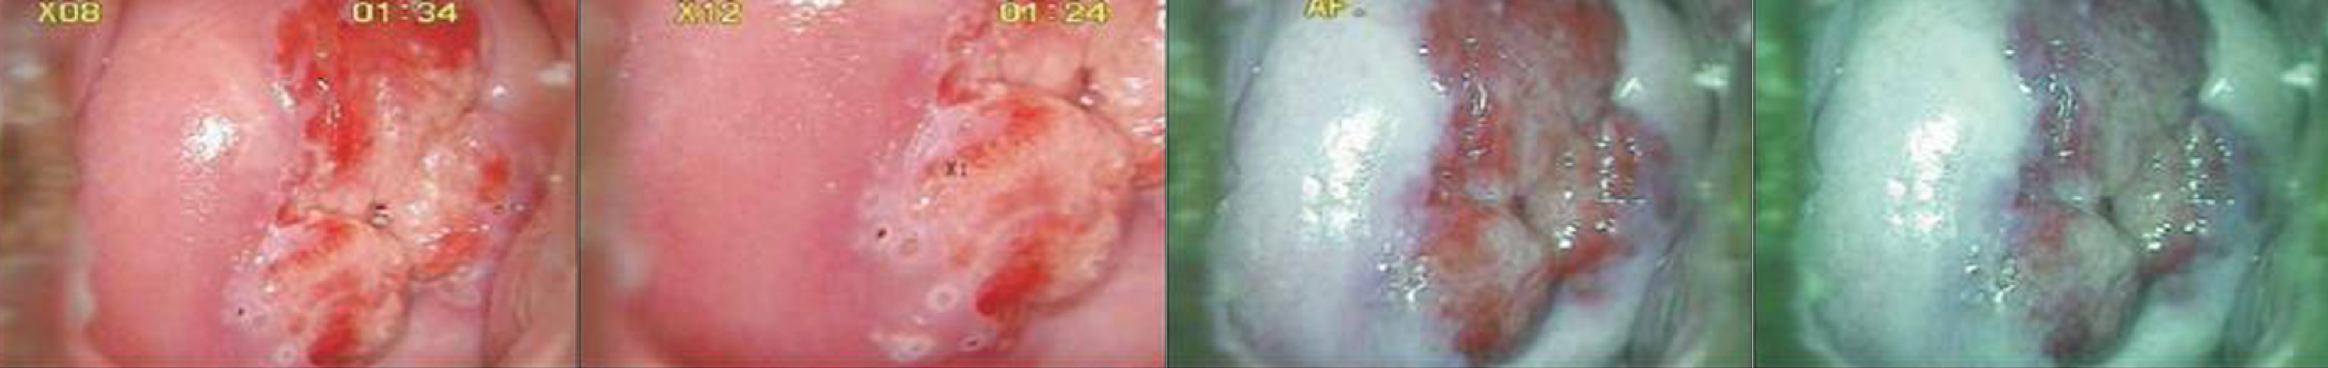

电子滤镜

通过滤镜更加直观识别组织

采用电子绿色滤镜功能,可有效识别上皮组织细节层次和细小血管的表现,满足临

床对早期癌变观察检查和诊断的需要